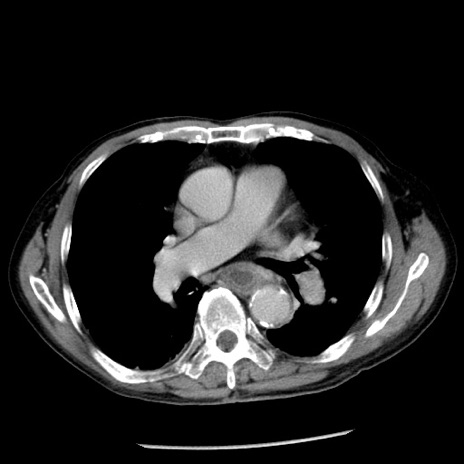

症例26(横断像)

【症例】80歳代男性

【主訴】嘔吐

【現病歴】昨晩2回嘔吐あり、今朝になっても嘔吐あり。来院。

【既往歴】胃潰瘍

【身体所見】意識清明、BT 37.6℃、BP 166/95mmHg、HR 100bpm、SpO2 97%、腹部:平坦・軟、腸蠕動音聴取良好、圧痛なし。

【データ】WBC 21900、CRP 1.46